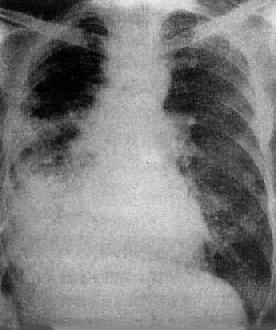

由于病灶系多次血行播散所形成,故X线表现为大小不一、密度不同、分布不均的多种性质的症灶(图3-1-23)。小者如粟粒,大者可为较大的结节状,主要分布于两肺上、中野,下野较少。早期播散的症灶可能已经钙化,而近期播散的病灶仍为增殖性或渗出性。本型结核发展较慢,经治疗新鲜病灶可以吸收,陈旧病灶多以纤维钙化而愈合。恶化时病灶可融合并形成空洞或逐渐转为慢性纤维空洞型肺结核。

图3-1-23 慢性血行播散型肺结核

两肺野布满大小不一、密度不同、分布不均的病灶,

下野较少,膈位置低而平